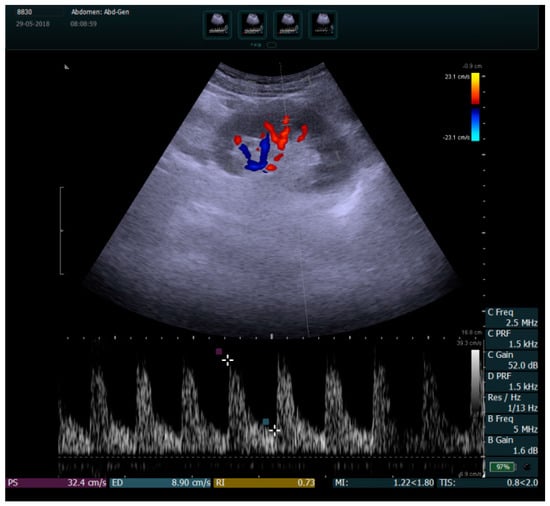

2.2.4. Measurement of Renal Vascular Damage